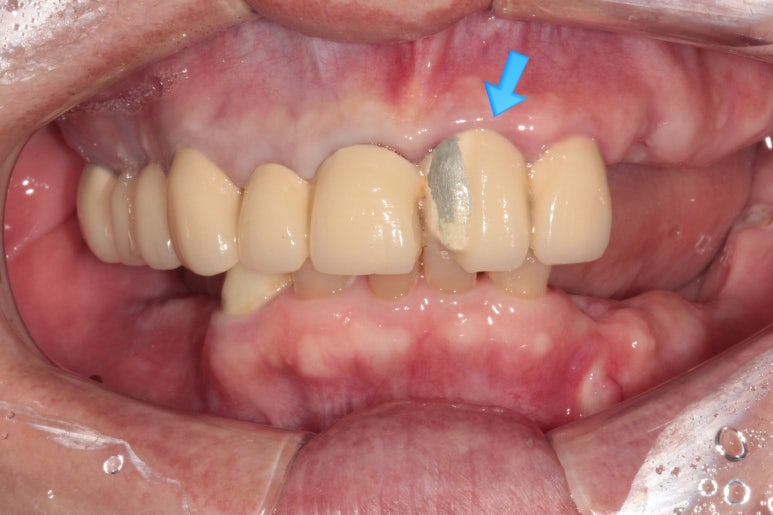

처음 오셨을 때 촬영한 정면 구강 내 사진입니다.

위 앞니 보철물은 도재 (포세린,porcelain)가 깨져있어 보기 흉한 상태였고, 대부분의 어금니가 없으신 상황..

지금까지 어떻게 식사하셨을까요 ㅠㅠ